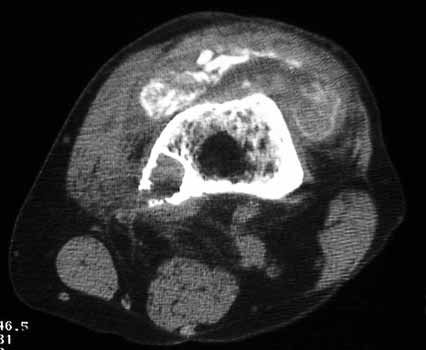

OSTEOLYSIS

Multifocal and massive, involving Gruen zone III of acetabular cup and Grune zone 1,2, and 6 of femoral component

Radiograph and CT

CT guided biopsy